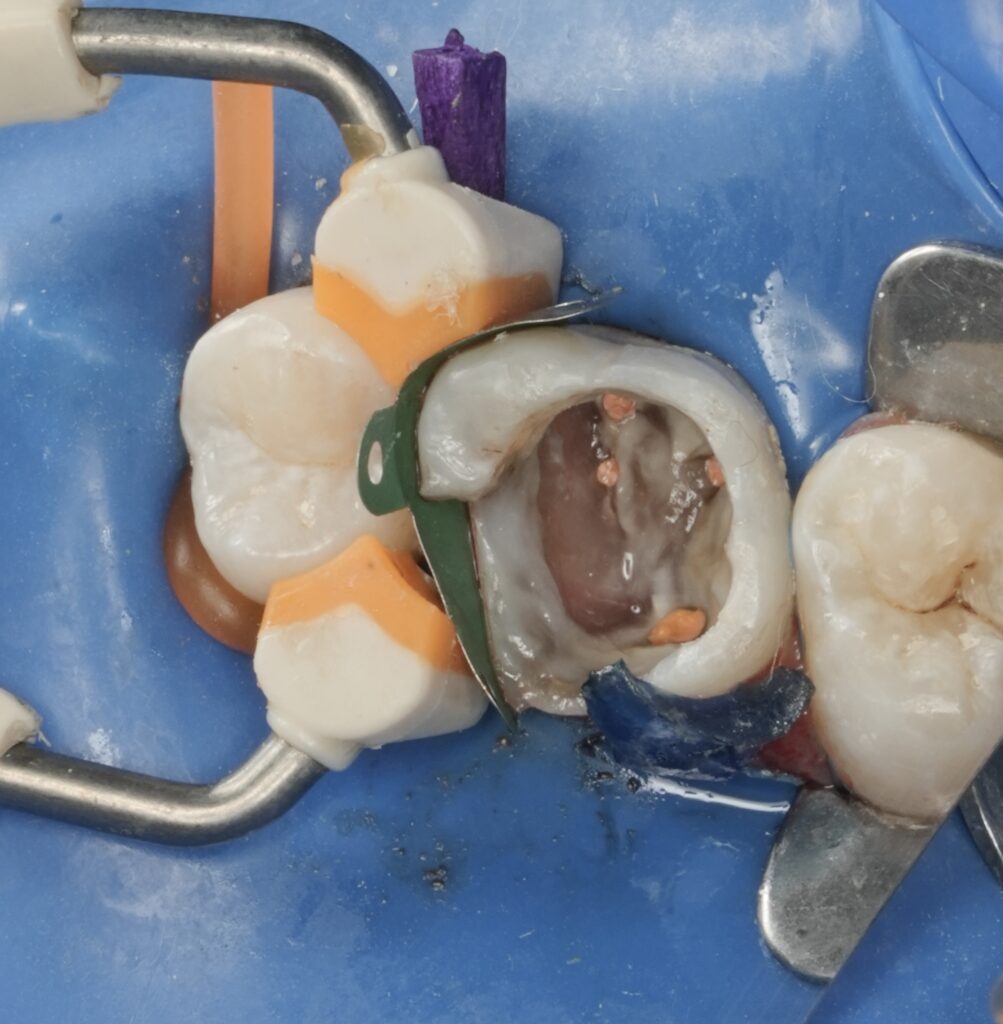

Endodontic Phase

After profound anesthesia, the tooth was isolated under rubber dam, ensuring absolute moisture control and asepsis. Access cavity preparation was performed conservatively, respecting pericervical dentin.

Special attention was given to canal location, particularly the mesiobuccal complex, where anatomical variations are common. Enhanced magnification allowed careful identification, negotiation, and shaping of all canals while minimizing unnecessary dentin removal.

Cleaning and shaping followed a biologically driven protocol, emphasizing effective irrigation, canal disinfection, and preservation of original canal anatomy. Obturation was completed to provide a three-dimensional seal, creating a stable foundation for immediate restorative procedures.